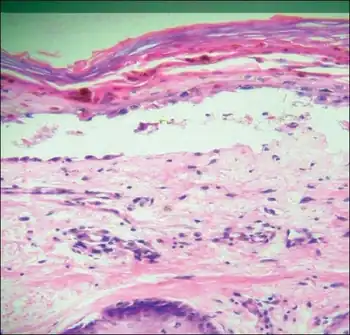

Transfusion associated graft versus host disease -Mononuclear cell infiltration and inflammation of affected epithelium, with focal vacuolation of basal epithelial cells

TA-GvHD can be suspected from a biopsy of the affected skin or liver,[3] and established by HLA analysis of the circulating lymphocytes. This testing can identify circulating lymphocytes with a different HLA type than the tissue cells of the host.